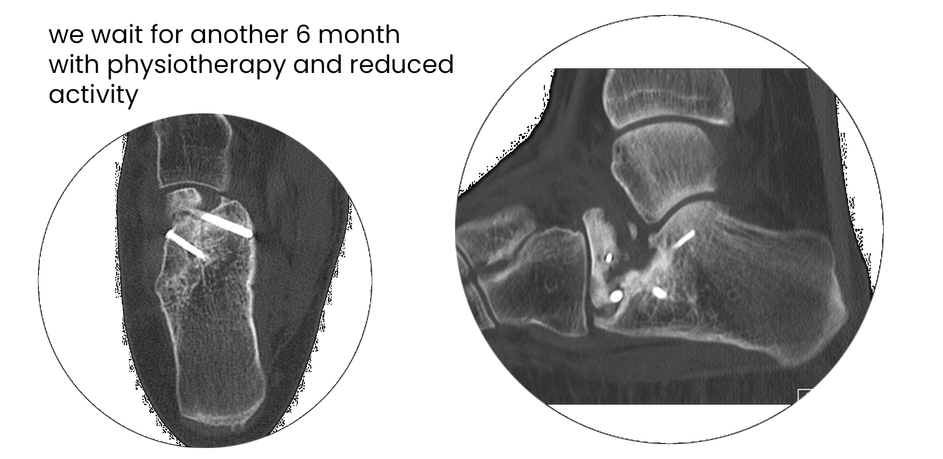

case 17LC, 29 years old, female, fall from horse

with the foot caught in the stirrup

"atypical fracture", surgery 19 hours after trauma